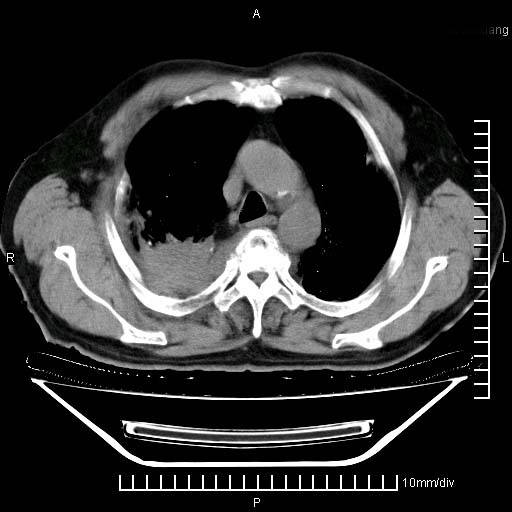

标题: CT24043:胸部增强:男性,60岁

既往肺结核,近10几天,咳嗽,咳痰,右侧胸痛,疼痛较明显,右上肺斑块考虑结核灶胸膜粘连,增强,可惜动脉期没有定好,未见强化,可延迟4分后又见较明显强化,中心见低密度影,如果说结核是边缘强化,可这个灶强化的面积挺大的,让人很挠头。

肺结核、胸膜增厚。

1)两肺继发性肺结核。2)右侧胸膜增厚+少量胸腔积液。